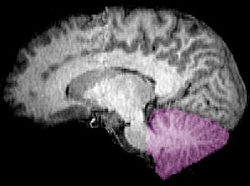

| Figure 1b: MRI image showing a mid- sagittal view of the human brain, with the cerebellum in purple. | ||

The cerebellum is located in the inferior posterior portion of the head (the hindbrain), directly dorsal to the pons, and inferior to the occipital lobe (Figs. 1 and 3). Because of its large number of tiny granule cells, the cerebellum contains more than 50% of all neurons in the brain, but it only takes up 10% of total brain volume. The cerebellum receives nearly 200 million input fibers; in contrast, the optic nerve is composed of a mere one million fibers.